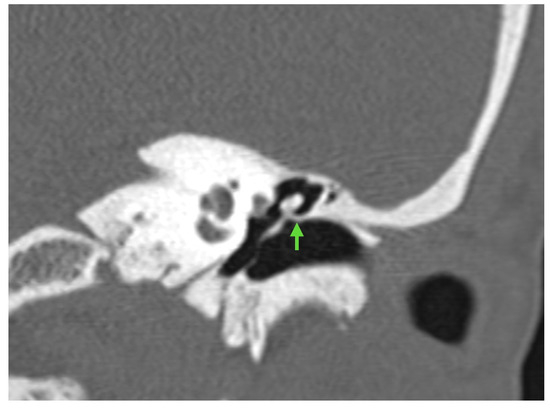

After an initial subjective and audiometric improvement, bilateral subjective hearing deterioration began 2 years later. The patient was referred to our center, where a mild-to-moderate bilateral mixed hearing loss was assessed, with a more pronounced deficit in the left side at 1000 Hz. CT imaging revealed erosion of the right long process of the incus and a bony bridge connecting the malleolar neck to the scutum on the left (Figure 1). Due to the patient’s perception of worsened hearing on the right side, she first underwent right stapedectomy revision, which revealed erosion of the long process of the incus at the site where the prosthesis loop was anchored.

Figure 1. The figure shows the preoperative CT scan, where a bony bridge connecting the malleolar neck to the scutum on the left is clearly visible (indicated by the green arrow).